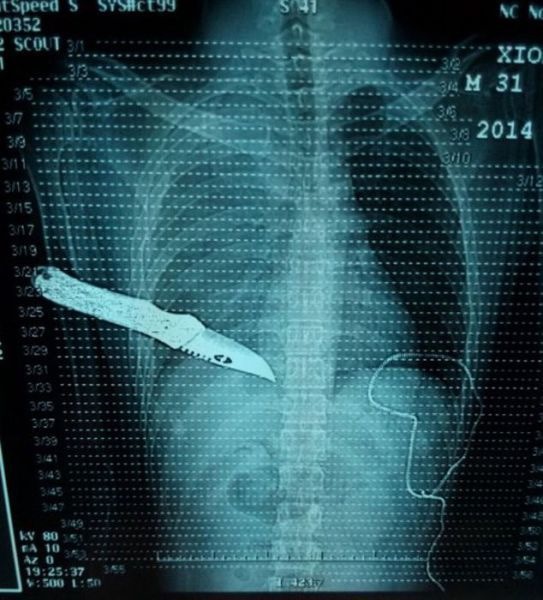

Необычные рентгеновские снимки: то, что скрыто внутри

Раздел: Визуальный дайджест